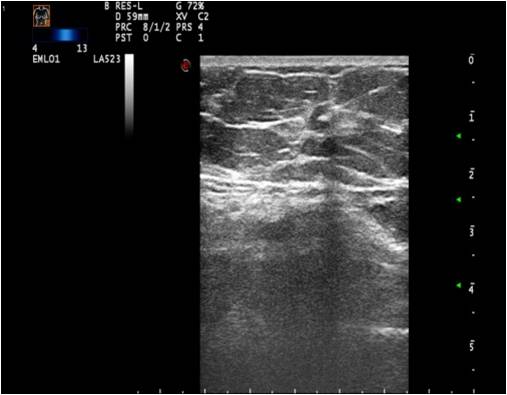

12.2.2.2. Breast Ultrasonography:

The examination is started with ultrasound under the age of 30. For women above 35 years of age it is the complimentary examination of mammography, while for women of 30-35 years we choose the first modality depending on the symptoms of the patient. In breasts of greater volume, mammography couldn’t be skipped.US is used as primary examination during pregnancy and lactation, as well as in patients with acute phase inflammatory processes.

Technical requirements: a high resolution linear head of 7.5 MHz, with a maximum length of 4-5 cm. A second supplementary head of 12-18 MHz is also recommended. The examination needs to be archived.